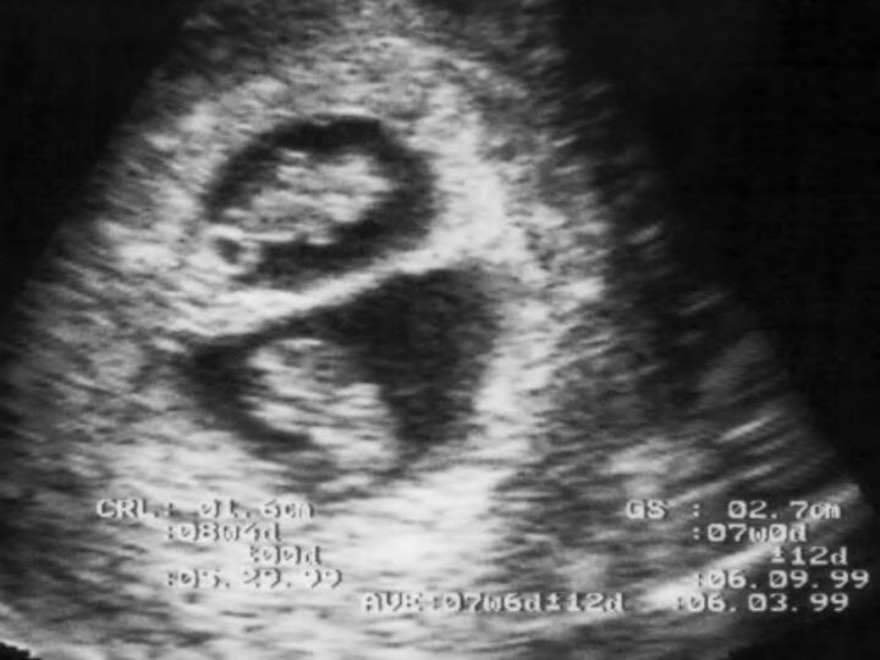

A pregnant lady comes for a routine antenatal checkup during the first trimester. USG examination reveals the following finding. Identify the type of twins in this patient.

The given scenario is suggestive of dichorionic, diamniotic twins. The image shows two separate amniotic cavities (diamniotic) and lambda sign (dichorionic).

In dichorionic twins, there is a thick triangular projection of placental tissue between the two gestational sacs. This is known as the lambda sign or twin peak sign. The following image shows the lambda/twin peak.

Dichorial, diamniotic twins can occur in 2 instances:

Dizygotic twins: The two fertilized ova get implanted at two separate sites and develop separate chorion and two separate amniotic cavities

Monozygotic twins: With early blastomere separation (up to 3rd day after fertilization), the two embryos formed will have separate chorionic and amniotic sacs, similar to dizygotic twins.